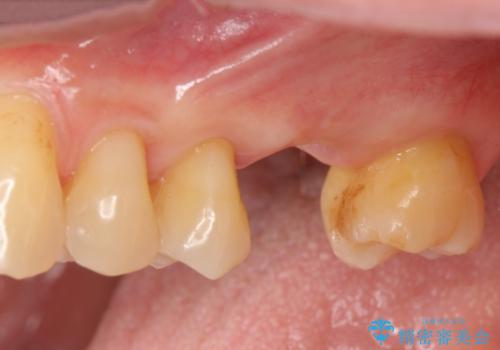

[ 失った歯の機能を回復 ] 奥歯のインプラント治療